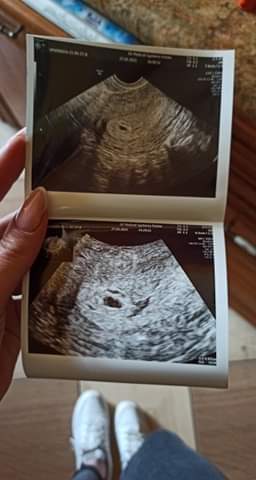

Też na Twoim miejscu powtórzyłabym betę. ja w poprzedniej ciąży miałam betę 560 na dwa/trzy dni przed wizytą i było widać pęcherzyk, ale wartość mogła być właśnie bliska 1000. Trzymam kciuki.

Załączniki

• received_2704199779819250.jpeg

received_2704199779819250.jpeg

16 KB · Wyświetleń: 185

Beta betą, ale poszłabym prywatnie na USG do jakiejś dobrej kliniki, bo faktycznie dziwny i kształt na USG i wynik bety, która nie rośnie, a lekarz widzi pęcherzyk...